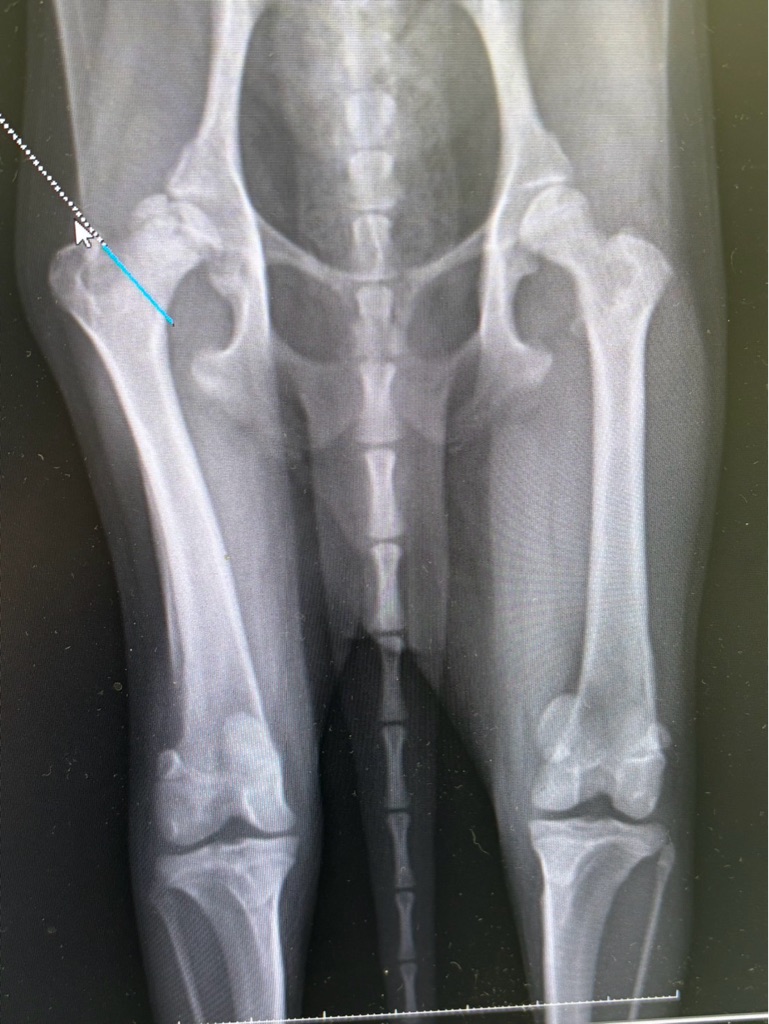

この子は レッグペルテスという病気です、

大腿骨の骨頭が壊死してしまうので 段々と歩くのも辛くなります。

ライアンは レッグペルテスで骨頭部を

切る手術になりました、